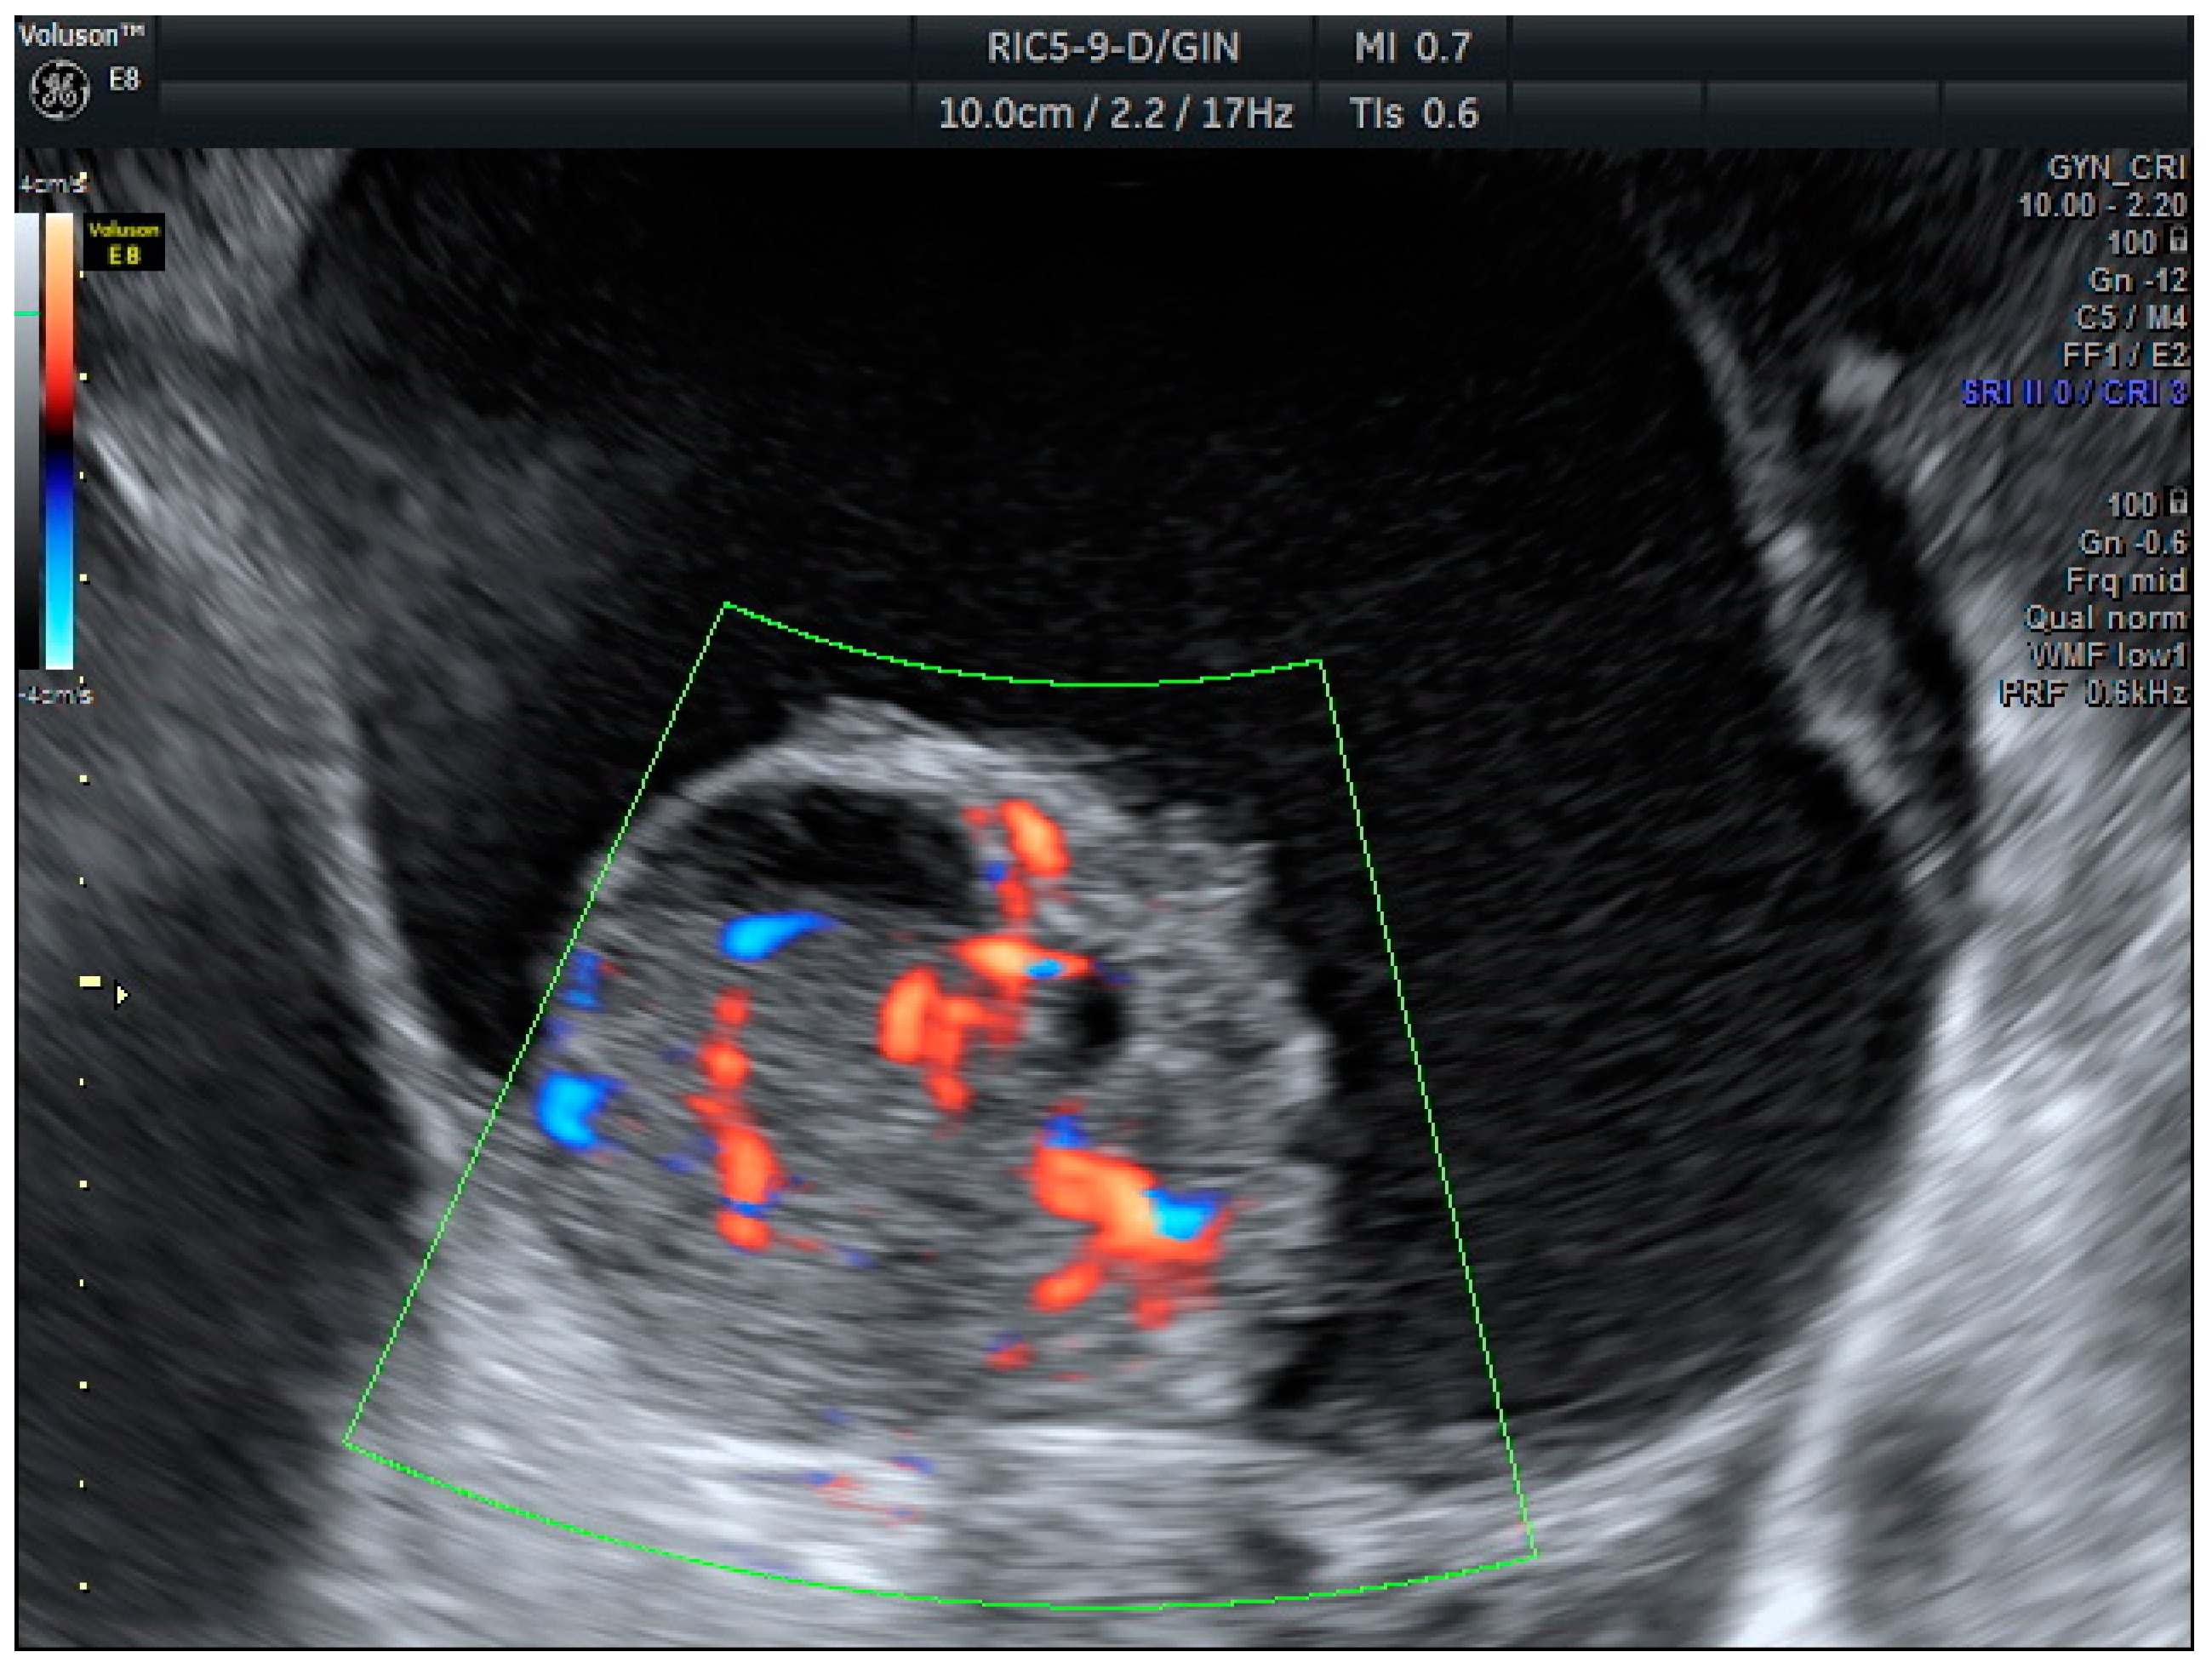

Years later, in 2008, the IOTA Simple Rules (SR) were among the first systems to provide a standardized framework for classifying adnexal masses based on ten rules. The benignity features (B) included unilocular cysts (B1) solid components < 7 mm (B2), acoustic shadows (B3), regular multilocular tumor < 100 mm (B4), and negative color maps (B5). The malignancy features (M) contained irregular solid tumors (M1), ascites (M2), ≥4 papillae (M3), multilocular irregular solid tumors > 100 mm (M4), and high vascularization (M5) (Figure 1 and Figure 2). According to SR, masses are classified as malignant if one or more malignancy features are present and no benignity features are observed; benign if one or more benignity features are present and no malignancy features are observed; and inconclusive if both types of features or none are present [5]. These rules have been extensively validated in the literature and have been shown to have good diagnostic performance [6,7]. In 2016, the IOTA Simple Rules Assessment was developed, integrating the Simple Rules with the consideration of whether the patient was treated at an oncology center, improving diagnostic accuracy [8], and adding a percentage of the probability of malignancy.

Figure 1. Mucinous carcinoma: Unilocular cystic mass with a solid-cystic papilla inside, showing extensive vascularization (score color 4).